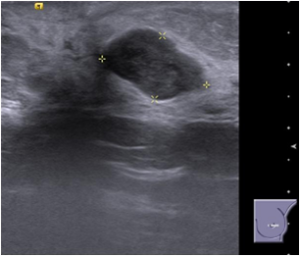

Bilateral Mammograms revealed increased reticular densities in the upper half of the right breast. A 16 mm well defined nodule seen in the left subareolar region. BIRADS 3/4 Bilateral breast ultrasound revealed extensively dilated ducts showing thickened walls and intra ductal contents corresponding to the increased reticular densities on the mammogram of right breast. Left breast revealed a 17 x 10 mm well defined low echogenic lesion with posterior enhancement in the left subareolar region. BIRADS 3 MRI showed segmental clumped / clustered ring enhancement extending from 10 to 2 O’ clock position in the right breast with extensive ductal branching and intraluminal contents extending till the nipple suspicious for DCIS. Left breast revealed a benign 16 x 14mm well defined nodule in the lower inner quadrant close to the nipple. BI-RADS-4.